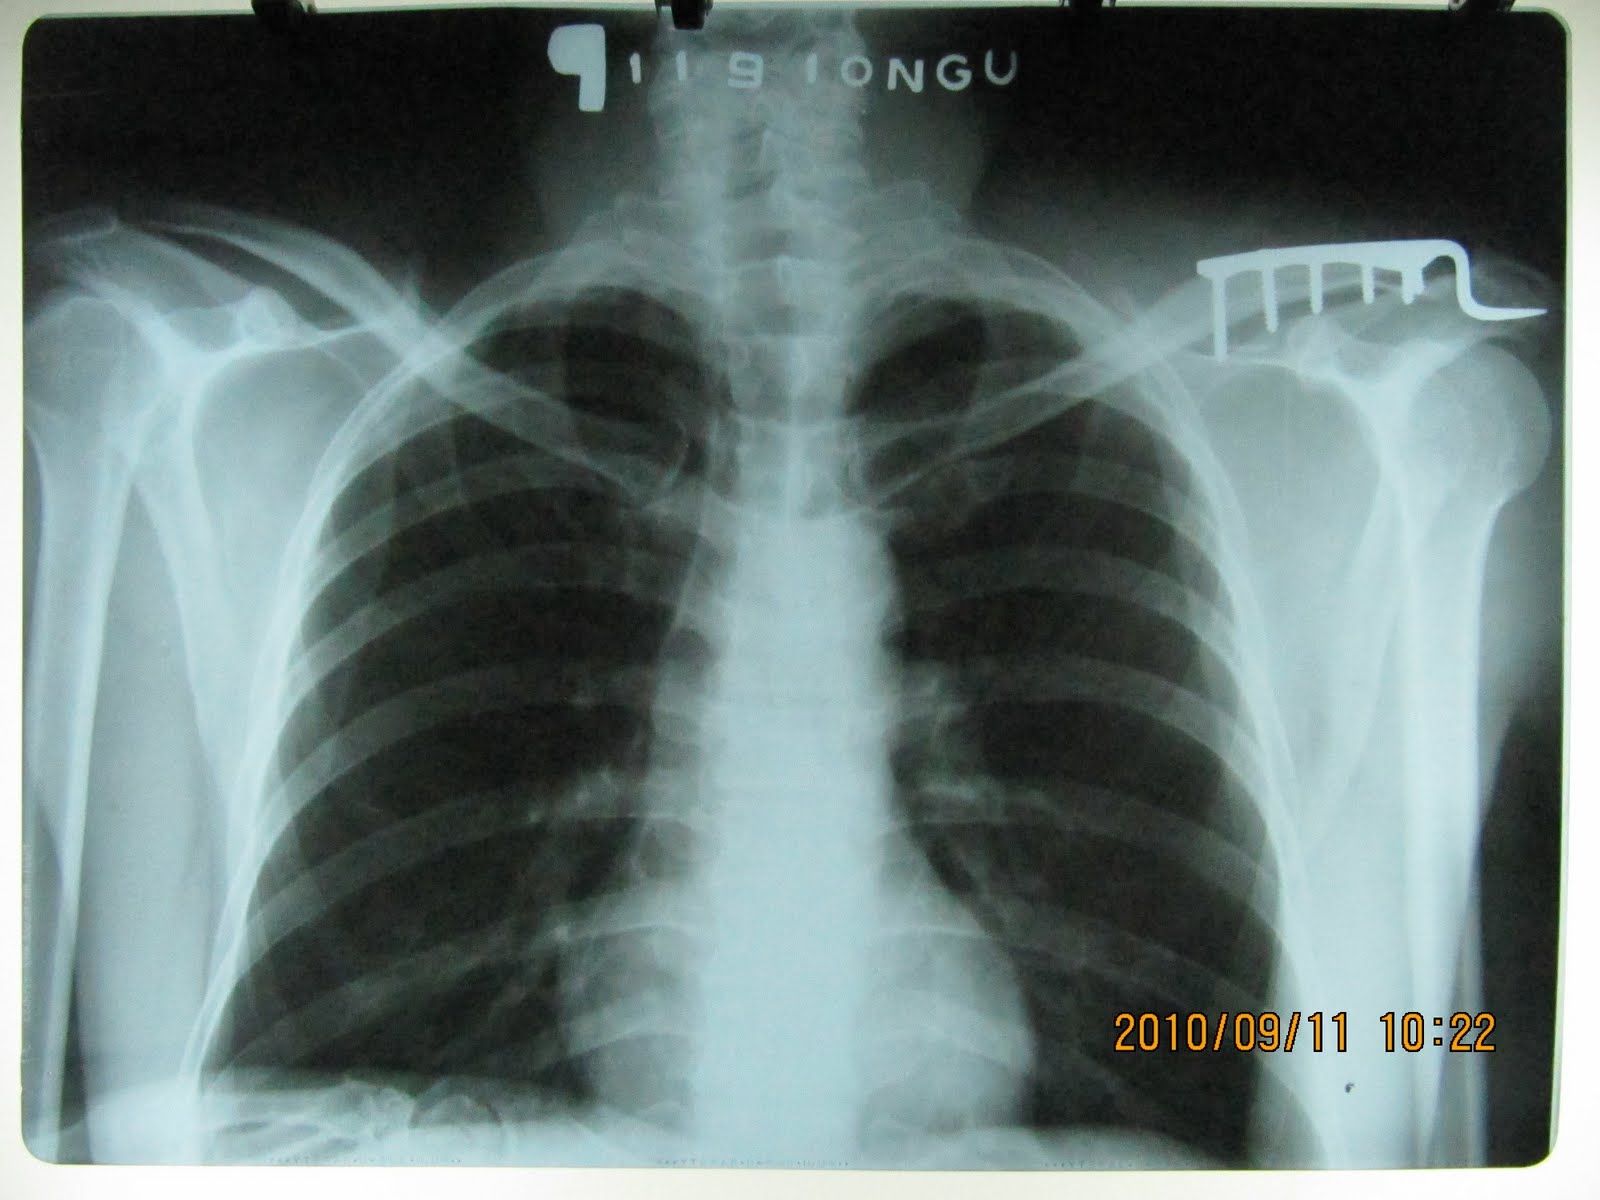

HÌNH ẢNH XQ SAU PT